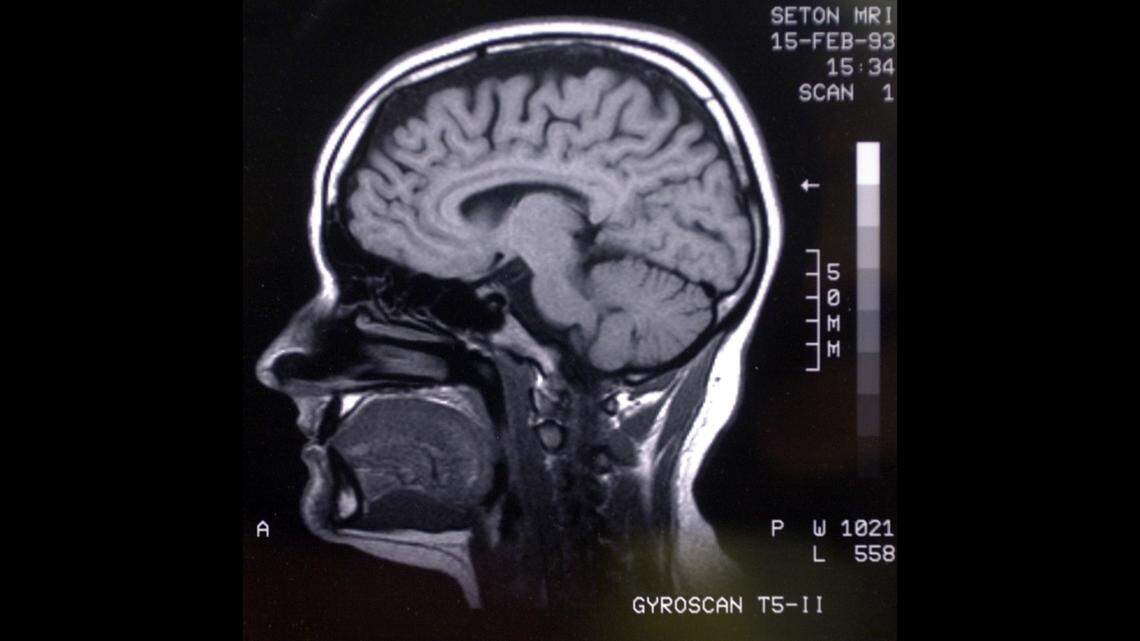

A brewing mystery has plagued a New Jersey high school after more than 100 former students and staff say they’ve developed rare brain tumors.

At the time, he detailed how his 44-year-old sister recently died due to a “very rare and highly aggressive malignant glioma brain tumor” — Glioblastoma Multiforme — found on the left side of her brain. She graduated from the school, which was built in 1967, in 1995.

She was diagnosed in August 2021 on the same day his wife, who graduated in 1991 and was told she had a “very rare brain tumor called an Acoustic Neuroma (aka Vestibular Schwannoma) on her left side,” Lupiano wrote.

“Why is this alarming? In 1999, I too was diagnosed with a very rare brain tumor on my left side. This now makes three of us in one family with primary brain tumors – all on the left side,” he wrote.

The American Cancer Society reports “the best known environmental risk factor for brain tumors is radiation exposure” and that “radiation-induced tumors” are rare.